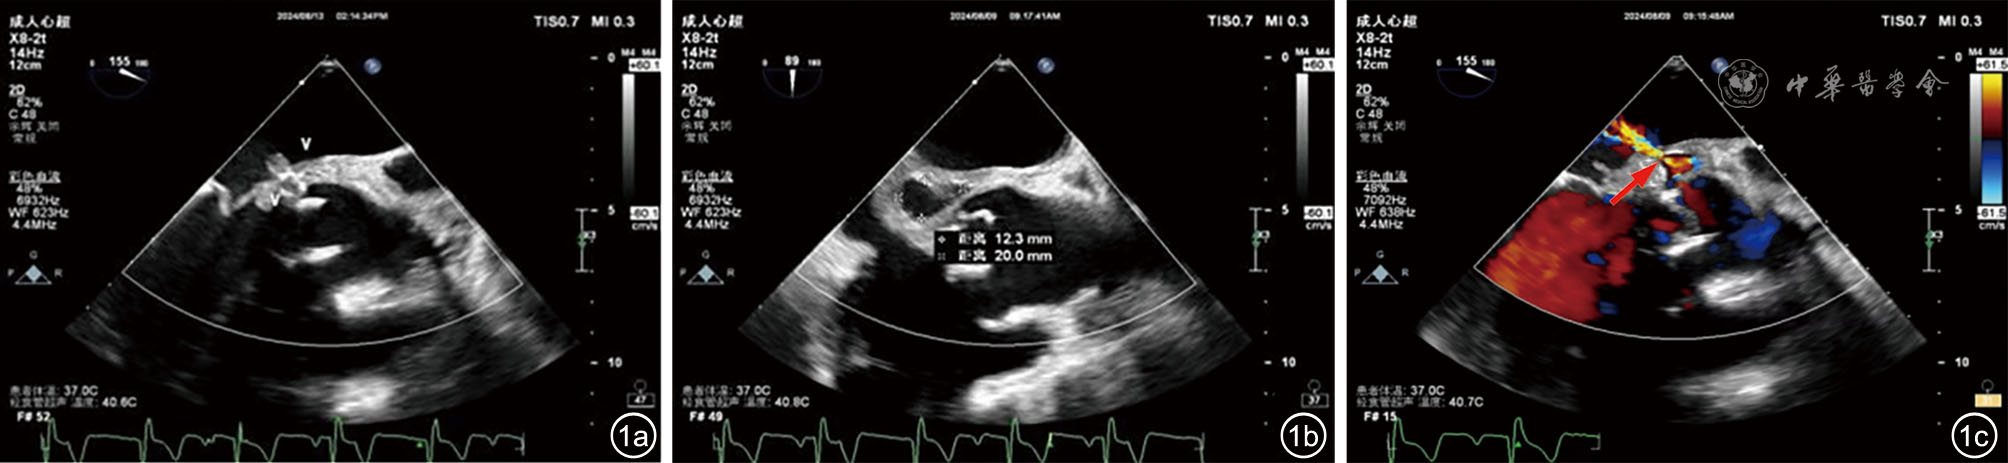

图1 患者经胸及经食管超声心动图检查图像。人工生物二尖瓣前叶的左心房侧与左心室侧均可见大小约9 mm×5 mm的中等回声附着,呈钟摆样活动(图中标“V”,图a),主动脉瓣与二尖瓣前叶连接处可见大小约20 mm×12 mm无回声区(图b),其内可探及血流信号,其中一束血流流入左心房,血流束宽约4 mm(红色箭头),最大流速约524 cm/s,压差约110 mmHg,另一束血流流入左心室流出道(图c)